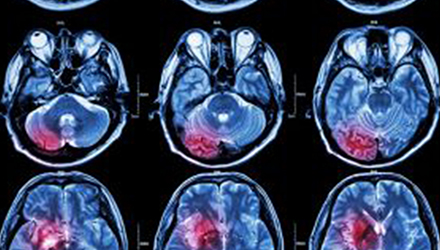

在這項(xiàng)研究中,研究人員使用功能核磁共振成像(fMRI)觀察大腦中血液含氧量的變化。研究人員首先研究了耳鳴患者和無(wú)耳鳴者的大腦活動(dòng),其目的是比較兩組受試者大腦處理情緒的方式。

在功能磁共振成像檢查中,受試者分別聽30種“愉悅”的聲音、30種“不愉快”的聲音和30種“中性”的聲音。這些聲音包括小孩咯咯笑,嬰兒啼哭,以及熱水壺?zé)_的聲音。

功能磁共振成像的結(jié)果顯示,當(dāng)暴露于情緒性聲音下,耳鳴患者大腦不同區(qū)域的活動(dòng)比沒(méi)有耳鳴者的活動(dòng)更強(qiáng)烈。接著,研究人員進(jìn)行了更深入的研究:耳鳴患者的大腦活躍性和耳鳴嚴(yán)重程度的關(guān)系。

調(diào)查結(jié)束后,再進(jìn)行功能核磁共振成像檢查。第二輪功能核磁共振成像顯示,那些耳鳴較輕的患者實(shí)際上使用了大腦不同的區(qū)域來(lái)處理情緒信息。

傳統(tǒng)觀點(diǎn)認(rèn)為,大腦中的扁桃體是處理情緒的關(guān)鍵,但此次研究發(fā)現(xiàn),那些不被耳鳴困擾的患者實(shí)際上使用更多大腦額葉來(lái)處理情緒。這類患者額葉活動(dòng)更顯著的原因是,額葉通常更多地用于注意力、計(jì)劃和沖動(dòng)的控制。